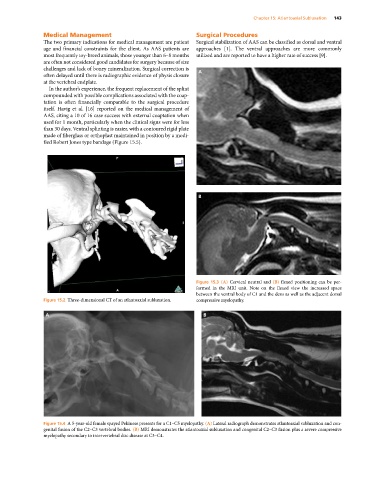

Figure 15.3 (A) Cervical neutral and (B) flexed positioning can be per-

formed in the MRI unit. Note on the flexed view the increased space

between the ventral body of C1 and the dens as well as the adjacent dorsal

Figure 15.2 Three‐dimensional CT of an atlantoaxial subluxation. compressive myelopathy.

Figure 15.4 A 5‐year‐old female spayed Pekinese presents for a C1–C5 myelopathy. (A) Lateral radiograph demonstrates atlantoaxial subluxation and con-

genital fusion of the C2–C3 vertebral bodies. (B) MRI demonstrates the atlantoaxial subluxation and congenital C2–C3 fusion plus a severe compressive

myelopathy secondary to intervertebral disc disease at C3–C4.